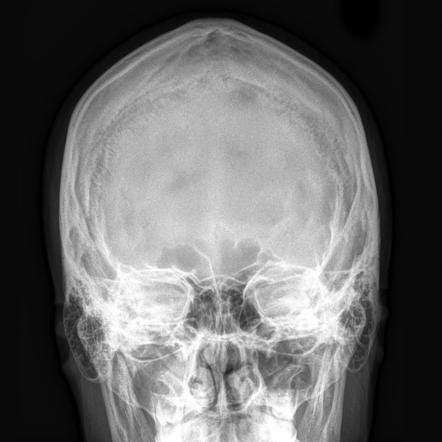

Radiographs, also known as “x-rays”

X-ray: x-rays, or “radiographs” use really high energy photons, that’s the same thing they were talking about when we’re talking about Light. Photons can be Red, photons can be Blue, photons can be really low power radio waves, and they can be really high power x-rays. When you take a really high power x-ray, which is a photon vibrating very very fast, with a higher frequency than even ultraviolet light, it can penetrate through the human body. Some of those x-rays will get absorbed on the way through, and others will not.

What determines whether they will go all the way through, and eventually hit a photographic plate on the other side?7 Well, if they hit something dense they’re more likely to be absorbed. If those photons hit something less dense, they cruise through. Bones are dense. Thus they are white on an x-ray because all those x-ray photons got absorbed and didn’t go through to the photographic plate on the back. When passing through the body containing muscle and blood vessels and brains and stuff, less of them get absorbed, and more of those photons hit a photographic plate. Like visual spectrum photons hitting a film negative, it gets darker. When we see x-ray radiographs, we’re looking at negatives, and unlike in photography, we don’t bother to flip the image so that white gets dark to the eye.

But that’s how we get an x-ray machine to make an x-ray picture. And then doctors can look at that and see what’s inside your body. We get the best resolution of bones — they’re the most dense.